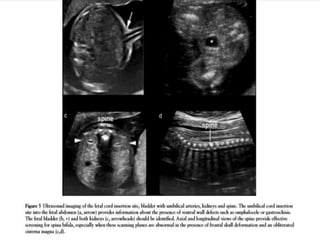

SPINA BIFIDA

Cranial Signs Associated With Open Spina Bifida